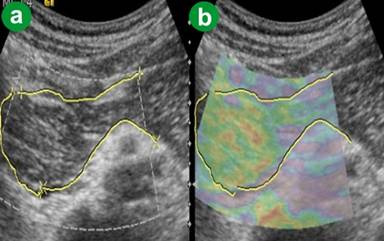

Acute and Acute Resolving Pancreatitic Group (Group 3)

In five patients (7.4% out of the 68 patients) the ARFI-VTQ values for pancreatic parenchyma and peripancreatic fat during the acute attack, or soon following an attack, were greater than the upper detection limit (ARFI-VTQ equal to 4.95 m/s) showing that the tissue hardness of this condition often is beyond the capacity of the machine. The 4.95 m/s value was arbitrarily assigned to these patients in order to allow the analysis of data. After considering this assumption, the ARFI-VTQ values for the pancreatic parenchyma ranged between 1.48 and 4.95 m/s with a mean of 3.283±0.852 m/s (Table 2, Figure 1). The mean ARFI-VTQ value for peripancreatic fat in this group was higher than 2.0 m/s. The eSie touch image colors ranged from light gray to dark black (scores 2-6) on gray scale (Figure 5). On color scale, the images ranged from yellowish green to dark red (scores 2-6) (Figure 5). Out of the 68 patients of this group, 48.5% (n=33) belonged to score 4 (yellowish red image), 35.3% (n=24) belonged to score 5 (patchy red image), 8.8% (n=6) had score 6 (dark red image), 1.5% (n=1) had score 3 (yellow image) and 5.9% (n=4) belonged to score 2 (yellowish green image).

Figure 5. Acute pancreatitis. a. US B-mode image. b. eSie touch color scale image (dark red: score 6). c. eSie touch gray scale image (dark black: score 6). |

The Follow-up of Patients

The eSie touch images for parenchyma and peripancreatic fat for the five patients with ARFI-VTQ values greater than the upper detection limit were dark black (score 6) on gray scale and dark red (score 6) on color image at the time of the acute attack, or soon following the attack. The numerical expression of tissue hardness (i.e. the fall below the upper detection limit of 4.95 m/s) in these patients was possible from the 7th day following attack. The ARFI-VTQ values during the following days decreased gradually reaching the value of 2.2 m/s (i.e., the highest ARFI-VTQ value observed in the healthy control group) within about 4-6 weeks depending upon the intensity of infection. During this period, the eSie touch images turned from dark black (score 6) to gray (score 3) on the gray scale image and from dark red (score 6) to yellow (score 3) on the color scale. There were patchy areas of light gray color and blue-green color on the respective scales, indicating necrosis (Figure 6).

Figure 6. Acute resolving pancreatitis with necrosis and pseudocyst formation in the body. a. US B-mode image. b. eSie touch color scale image: patchy red parenchyma with focal green/purple area suggesting necrosis and pseudocyst formation. |